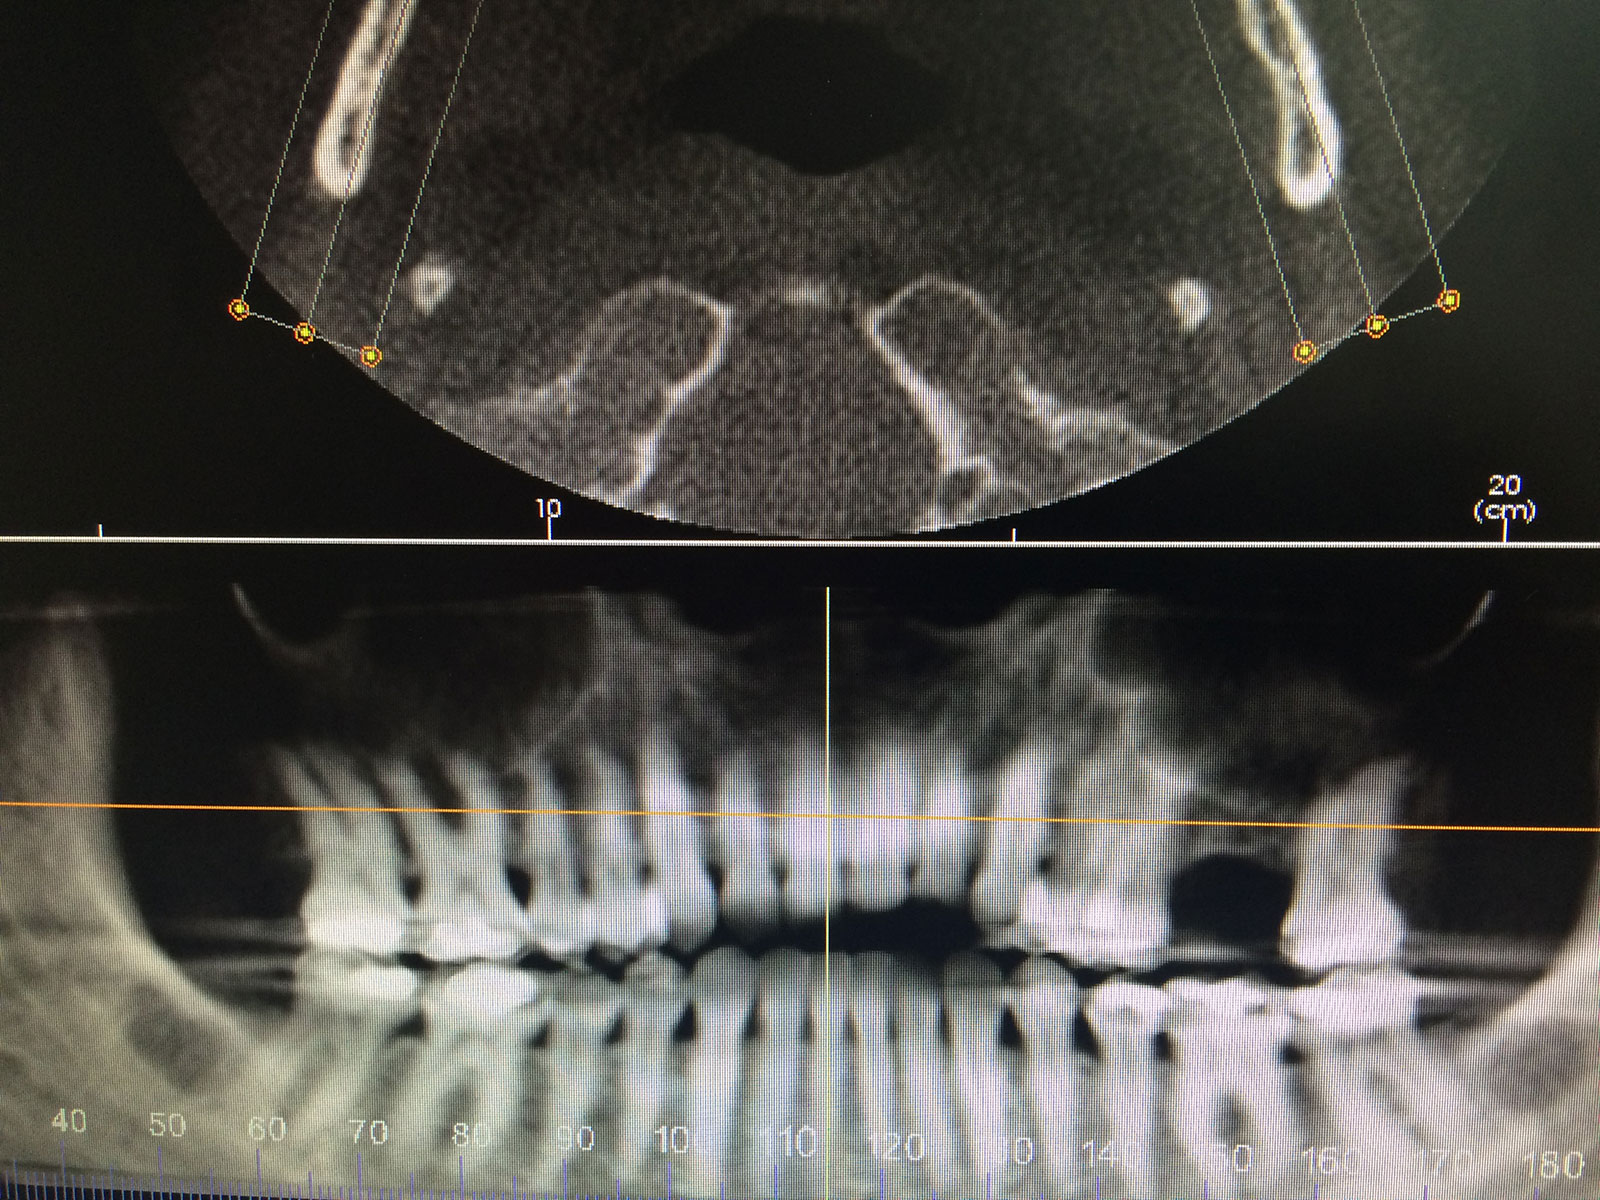

Sinus Grafting Procedures

A sinus grafting procedure, also known as a sinus augmentation, is for patients who have insufficient natural bone in the areas where dental implants are needed. They are long lasting, strong and sturdy, and fit and function like natural teeth. The procedure involves adding bone, either your own natural bone from another part of the body, from a donor or made of processed or synthetic bone material, and placing it below the sinus so that the implants can be placed. After the bone has healed and developed, usually around four to 12 months, the dental implants can be placed.

The photos on this website are from real surgeries performed by Dr. Ulloa. Due to the

graphic nature of the images and content, viewer discretion is advised.